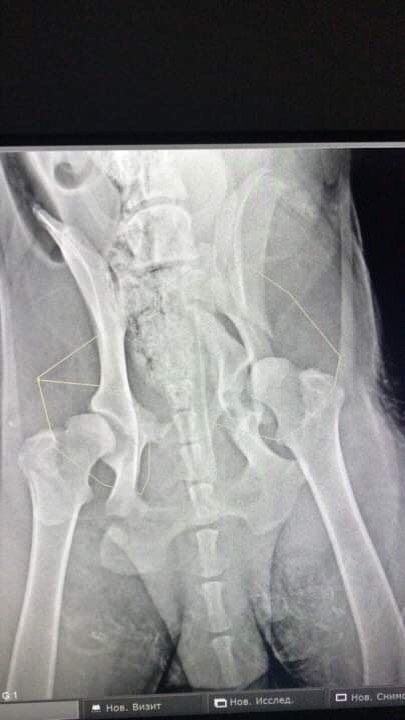

Двойной перелом таза без смещения. Чипа нет. Клеймо не рассмотреть -очень волосатое брюхо.

"надо показать снимки собаки специалистам,перелом со смещение,может надо оперировать и ставить пластину"

Обязательно надо но только после восстановления от пирика. А за эио время уже может успеть непоавильно сростисьДайвер писал(а):Мила, а что с тазом, оперировать не надо?

Фауста прооперировали